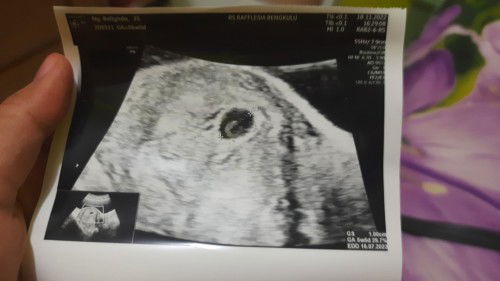

Hamil 6w baru trlihat kantung dan kuning telur saja

Bunda² disini ad yg prnh ngga kehamilan usia 6w cuma ad kantung sama kuning telur (yolk sac) ny aj tp besar. Apa it normal ya ? Ak jd tkt soalny liat komenan org kalo yolk sac besar tanda ny ngga normal.